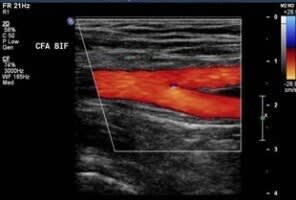

✓ Detection of PAD using Ultrasound

Peripheral arterial disease is from a narrowing or stenosis of the arteries which supply oxygenated blood to the legs. This is mainly caused by disease in the wall of arteries known as atheroma, which develops gradually over a length of time. It begins with cholesterol from the blood being deposited within the wall of arteries, leading to the thickening of the artery wall. This results in a narrowing or stenosis of the artery and a reduction of oxygenated blood flow to the leg.